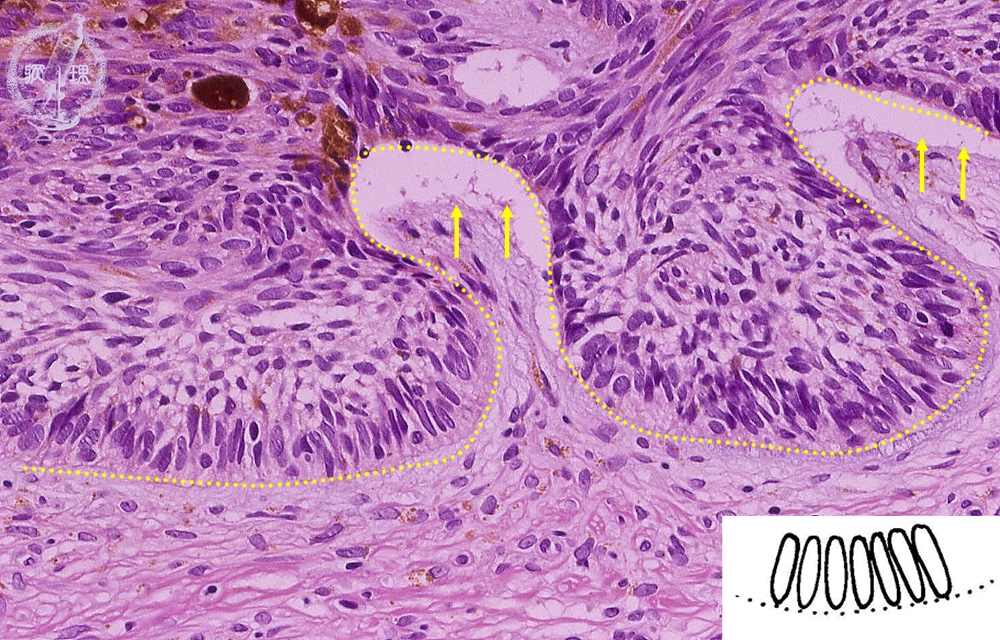

扁平上皮癌(浸潤癌)ミクロ像(HE中拡大)

ミクロ像(HE中拡大):扁平上皮癌は扁平上皮に由来する悪性腫瘍で、特に表皮の有棘細胞由来のものを有棘細胞癌という。真皮内へ浸潤している。